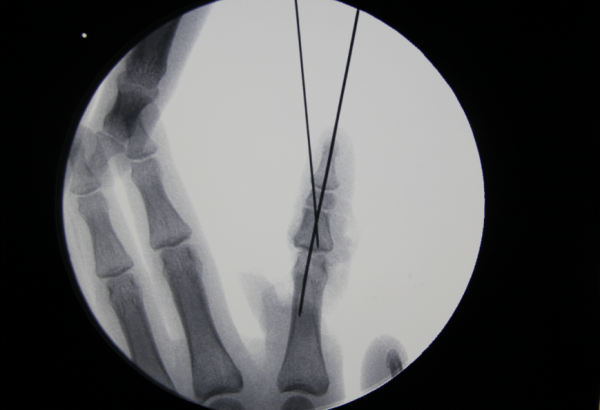

x线

跖趾关节成形